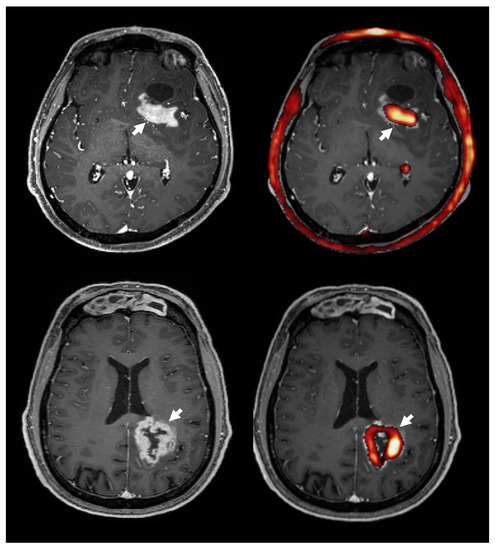

3.8. Choline PET Uptake vs. Contrast Enhanced T1 MRI

4.4. 18F-FMC PET vs. MRS